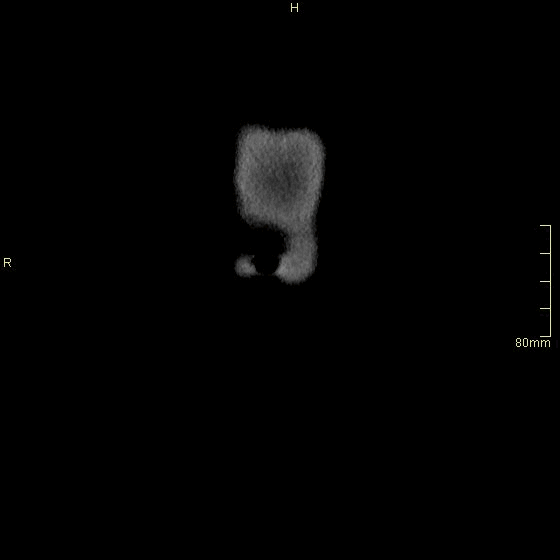

Chest Arterial (Sagittal)